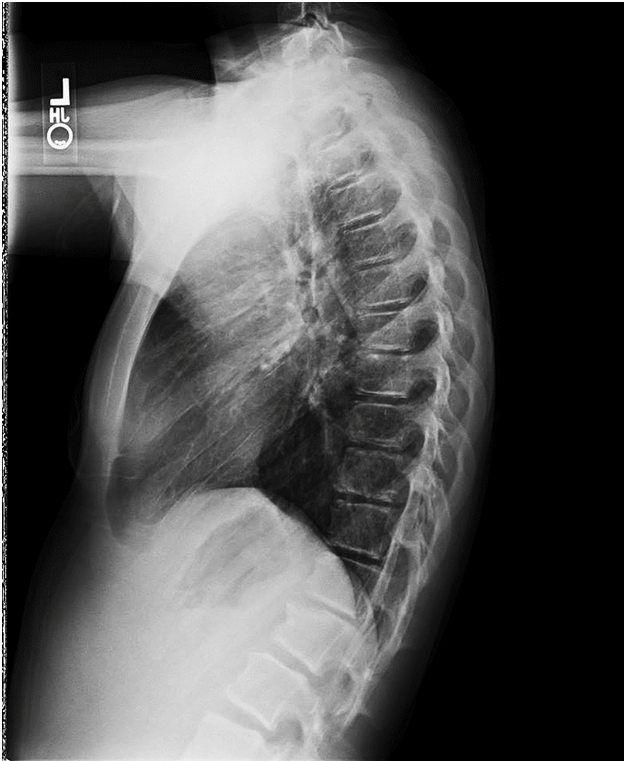

Does Scoliosis Cause Back Pain? Here’s What the Research (and Real Life) Tells Us

Back pain and scoliosis are often linked — but is scoliosis the actual cause of the pain? In this blog, we explore what current research says, why imbalances from spinal curves matter, and how targeted treatment like the Schroth Method can help reduce pain and restore balance. Whether you’re a concerned parent or an adult navigating scoliosis-related discomfort, this guide offers clarity, science-backed insights, and practical next steps to feel better and move forward.